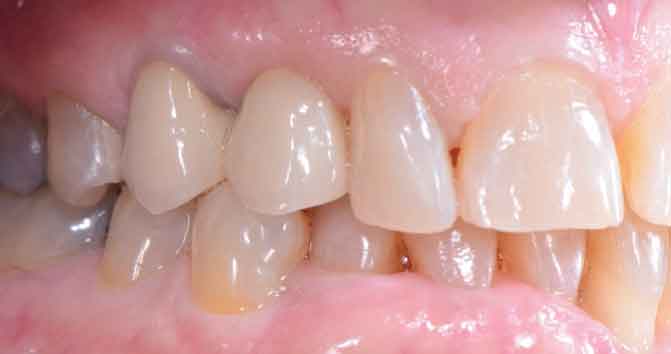

Return to "Modern Applications for The Cantilever Fixed Partial Denture" partial-denture-1 Next Previous